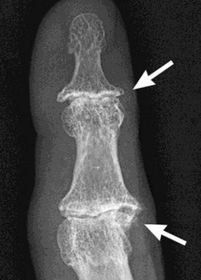

What disease is this? What do the arrows indicate? | Gout Arrows = 'punched out' erosions |

What disease is this? What indicates this? | Tophaceous gout. Soft tissue swelling surrounding the index finger PIPJ, with associated erosion and bone resorption |

What disease is this? | Tophaceous gout. |